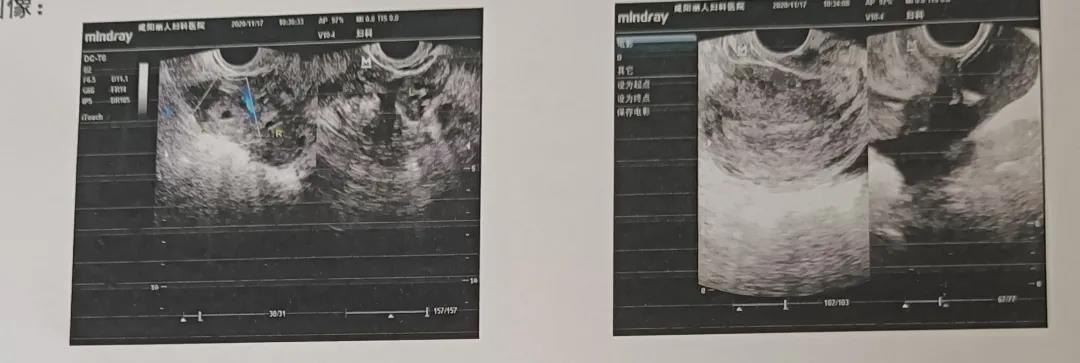

子宫:前位。宫体大小为56x52x43mm,形态规则,包膜完整,肌壁回声均匀,内膜厚9mm。

附件:左侧附件区未见明显异常。右侧卵巢大小约34X26mm,其旁可探及大小约27X22mm的混合性包块。

子宫直肠窝可见范围约65x26mm的不规则液性暗区,透声差。